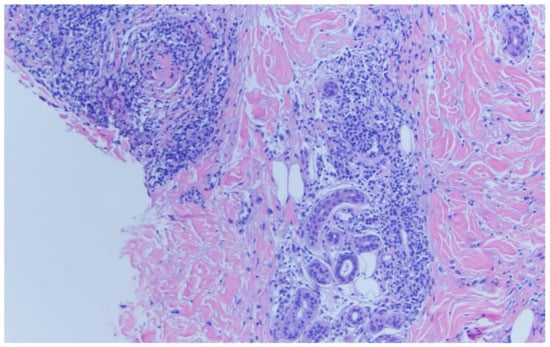

A shave biopsy was later performed of the right ear helix (Figure 4), about two months after initial presentation. This specimen demonstrates telangiectasia with a superficial perivascular lymphohistiocytic infiltrate. Immunohistochemical panel shows a normal ratio of CD4 and CD8 T cells, without evidence of chronic T cell lymphoma. There is no significant dermal mucin nor increased plasmacytoid dendritic cells, again pointing towards a connective tissue disease pathology.

Figure 4. Shave biopsy specimen from right ear helix.